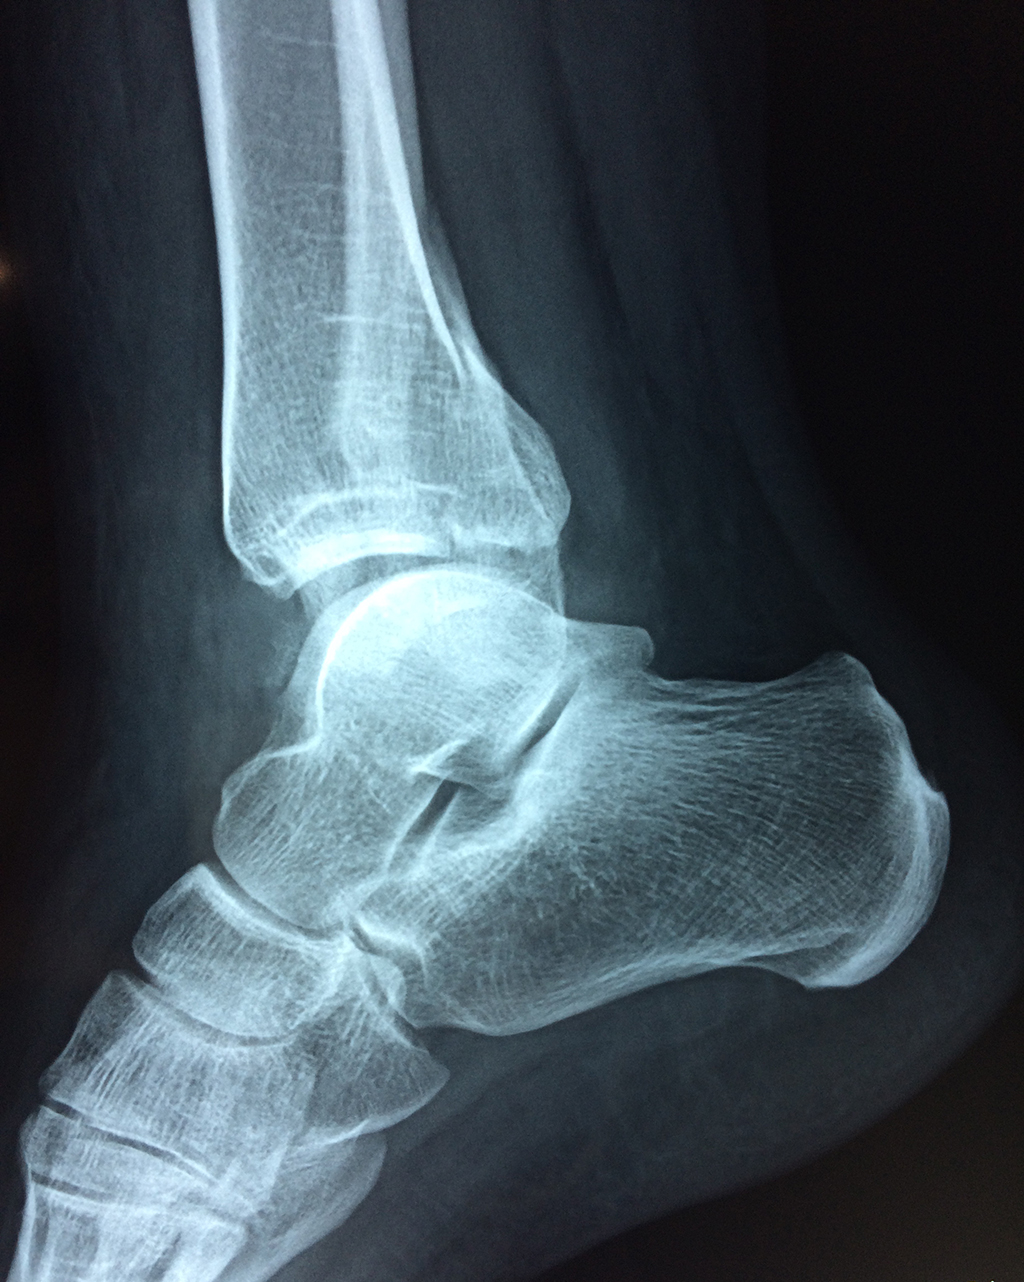

Una fractura de tobillo es la rotura de uno o más de los huesos del tobillo. Estas fracturas pueden ser:

- Parciales (el hueso está sólo parcialmente fisurado, no del todo).

- Completas (el hueso está perforado y está en 2 partes).

- Producirse en uno o ambos lados del tobillo.

Algunas fracturas de tobillo pueden requerir cirugía si:

- Los extremos de los huesos están desalineados entre sí (desplazados).

- La fractura se extiende hasta la articulación del tobillo (fractura intra-articular).